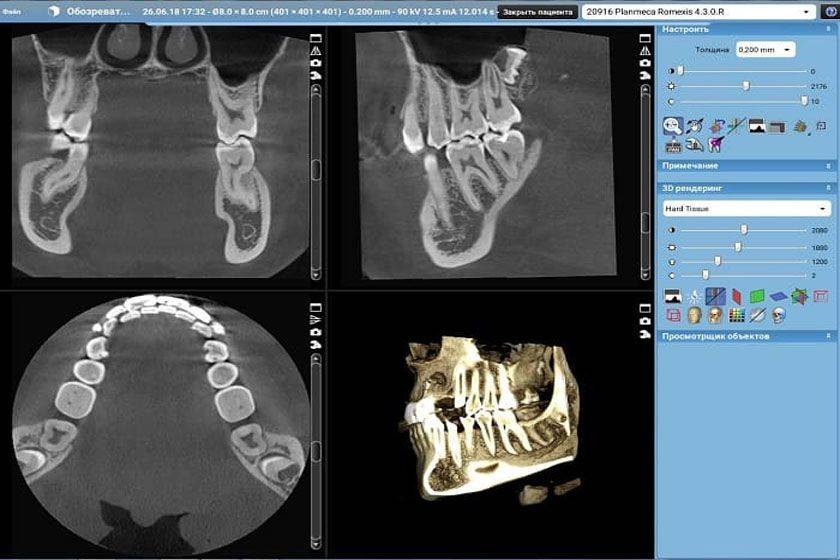

Где можно его сделать

В большинстве стоматологических клиник есть рентген-кабинет, где пациент может, не покидая здания, пройти эту процедуру и вернуться к своему стоматологу со снимками. В государственных клиниках тоже есть такие установки, но исключительно старого образца. Это означает, что процедуру придется проходить несколько раз и меньше заплатить. Также у старой аппаратуры большие дозы облучения. К сожалению, многие частные стоматологии также оснащены такой техникой. Иногда частный доктор может направить в другой диагностический центр для получения данных. Конусно-лучевая компьютерная томография бывает только в прогрессивных частных клиниках, однако точность результатов полностью себя окупает.

Цена на услугу будет зависеть от типа обследования. Так, прикусная рентгенография стоит от 3 до 10 долларов, в зависимости от количества снимков. При этом и в государственном, и в частном учреждении цены практически одинаковы. Панорамное изображение обойдется примерно в 20-25 долларов. Сделать его можно только в частных учреждениях, но некоторые из клиник могут предоставить такую услугу бесплатно, если пациент лечится у них. Самая дорогая диагностика – КЛКТ, делают ее в единичных диагностических и стоматологических центрах. Ее стоимость составит 50-60 долларов.

- в идеале следует посетить медицинское учреждение, специалисты которого практикуют использование визиографа (альтернатива рентгеновскому аппарату), преимущества которого: щадящее воздействие на организм, чувствительный датчик.

Результат использования визиографа – точное изображение зуба (с каждой стороны), минимальная доза излучения исключает негативные последствия. Даже при наличии сомнений относительно беременности необходимо сообщить лечащему врачу о предположении для назначения безопасного лечения.

Особенно актуально это тогда, когда в организм не попадает достаточное количество питательных элементов. Такое бывает по причине неправильного и несбалансированного питания, отсутствия в рационе овощей, свежих фруктов, зелени и т.п. Однако даже у здоровой девушки могут начать крошиться и разрушаться зубы, может ускориться процесс деминерализации эмали. В итоге может понадобиться томография, ведь только на объемном снимке можно оценить масштаб имеющейся проблемы.

О возможности использования аппарата должен принимать решение только квалифицированный рентгенолог и только на основании полученных в ходе предварительного осмотра данных. Одно можно сказать с уверенностью: нельзя делать снимки на старом оборудовании, которое дает слишком высокую дозу облучения. Предпочтение лучше отдавать современным визиографам, время воздействия которых не превышает пары секунд. Это на 100% безопасный и безболезненный метод.